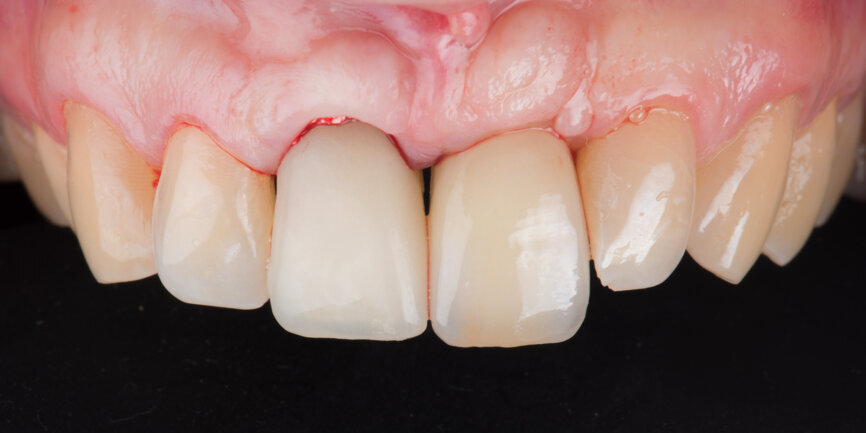

Prosthetic procedure

Two months after the extraction of tooth #12, an implant level impression was taken for final restoration using a digital scan body (Fig. 18) and a digital intra-oral scanner (TRIOS, 3Shape). A zirconia cantilevered fixed implant-supported bridge was fabricated according to a fully digital workflow (Figs. 19 & 20). The screw-retained bridge was then torqued to 35 N cm (Figs. 21 & 22). The follow-up, ten months after implant placement, showed a well-preserved gingival contour (Figs. 23 & 24).